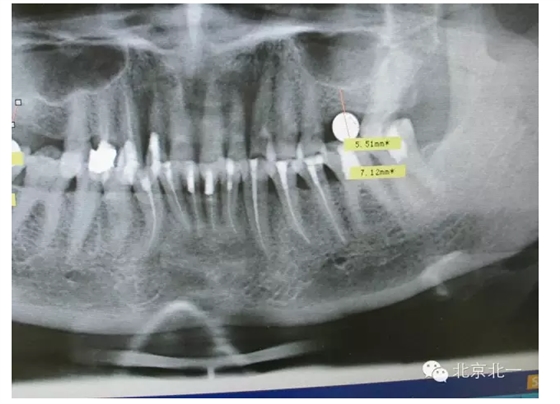

擅長:種植外科,尤其專長復雜牙種植,自體骨移植同期種植,上頜竇底內(nèi)外提升同期種植技術,美學區(qū)種植技術,即刻種植外科與即刻負重技術,軟組織成形外科種植技術及全口無牙頜ALL-ON-FOUR技術,種植并發(fā)癥和種植急癥處置等手術治療,從事口腔頜面外科,正頜外科、頜面部整形、微創(chuàng)拔牙,笑氣無痛舒適種植十余年。